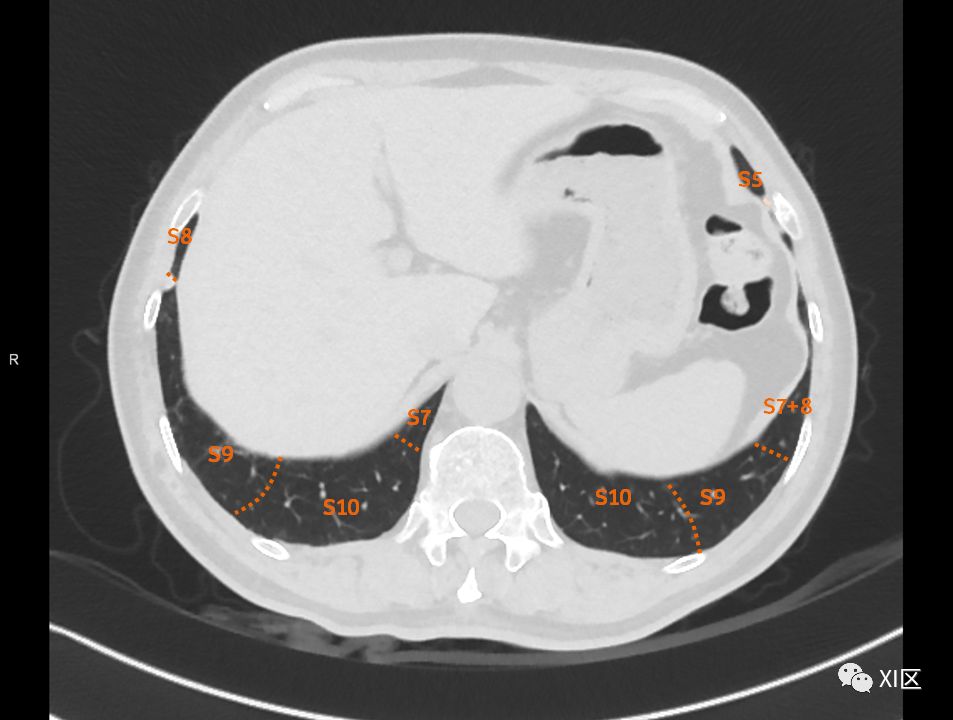

在进行肺的分段时,可以上下观察浏览,沿着相应气管的走形可以更容易准确地进行分段。

肺的断层分段示意图